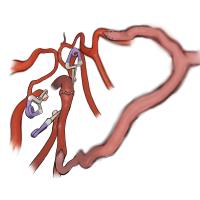

術後イラストシリーズ